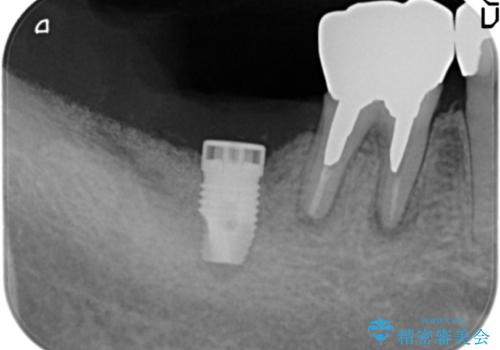

骨が少なくインプラントできないと言われた 下の奥歯のインプラント 60代男性

- 奥歯のインプラントをご希望し来院された患者様です。

骨が少なく下顎神経に近いことから、他院でインプラントできないと言われたとのことでした。

骨増生(GBR)を行い骨を増やすことでインプラント治療を可能にしました。

インプラントの種類:スプライン ツイスト (HAコーティング)

固定様式:セメント固定

クラウンの種類:オールセラミッククラウン スタンダード